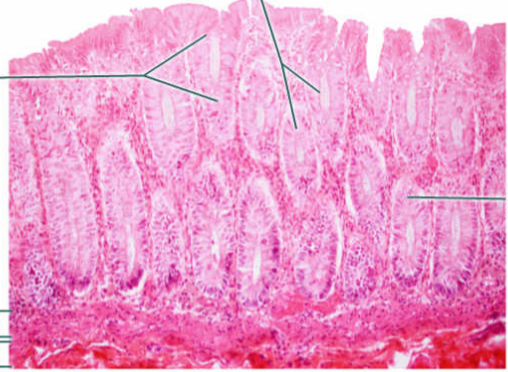

Area

Large intestine

Large circles

Goblet cells

Epithelium

Simple columnar